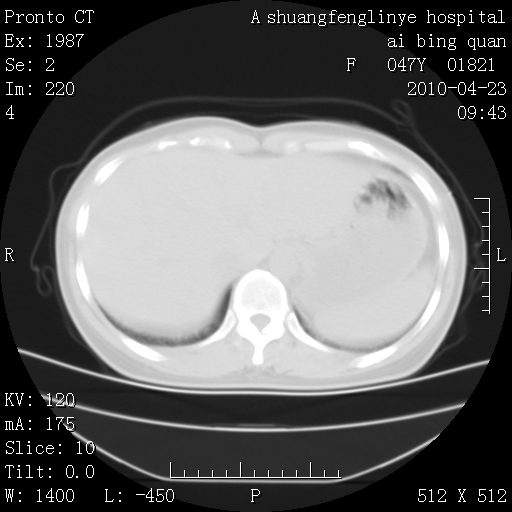

标题: CT25944:胸痛、气短、前几日高烧!肺Ca?请会诊! [打印本页]

标题: CT25944:胸痛、气短、前几日高烧!肺Ca?请会诊!

双肺多发结节,考虑转移瘤,肺癌肺转移不除外

双肺多发结节,部分密度较高,最大结节边缘光滑。临床有“胸痛、气短、前几日高烧”病史。首选考虑:右肺感染性病变!建议积极消炎后复查!

建议抗炎治疗后复查,排除肿瘤性病变。